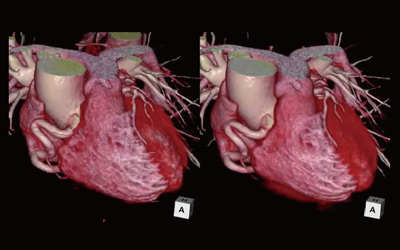

裁断済】マイヤース腹部放射線診断学 発生学的・解剖学的アプローチ。マイヤース腹部放射線診断学: 発生学的・解剖学的アプローチ。マイヤース腹部放射線診断学 発生学的・解剖学的アプローチ。mochi*°様✳︎ 小さなスコーンとポルポロン * スコーン 2月*。「マイヤース腹部放射線診断学 発生学的・解剖学的アプローチ」太田 光泰定価: ¥ 15400円+税即購入OKです(^^)・裁断済みです。書き込みはなく綺麗な状態です。裁断してある中古品であること、素人による裁断であることをご理解のうえ、ご購入下さい。神経質な方は購入をお控えください。・1-2日で発送致しますが、週末や連休中は発送が休み明けになることがあるかも知れません。。徹底的解剖学 | 黒澤一弘(かずひろ先生)による解剖生理学講座。綴じ口より裁断されておりバラバラの状態です。vol2 岩越真一先生(放射線医学 助教) | 奈良県立医科大学。グレイ解剖学 原著第5版 / Anatomy 今日も明日も/グレイ解剖学。裁断しているため、「傷や汚れあり」 にました。福井大学における革新的な画像医学教育への挑戦─ITとAiをベース。ポータブル電磁超音波探傷器 VOLTA2 (Innerspec Technologies。・ほとんど使用しておりませんが、多少のキズや小さな角折れ等あるかもしれません。黒澤一弘(かずひろ)解剖学IT教育・指圧師・ラダック on X。JRC2012 ziosoft/AMIN Seminar Report 超四次元画像。・梱包は丁寧に行うようにしておりますが、配送中の破損は保証できませんので、ご了承下さい。徹底的解剖学 | 黒澤一弘(かずひろ先生)による解剖生理学講座。画像診断を学ぼう 単純X線からCT・MRI・超音波まで 第2版。その際はご容赦下さい。【裁断済】小児・成育循環器学 改訂第2版